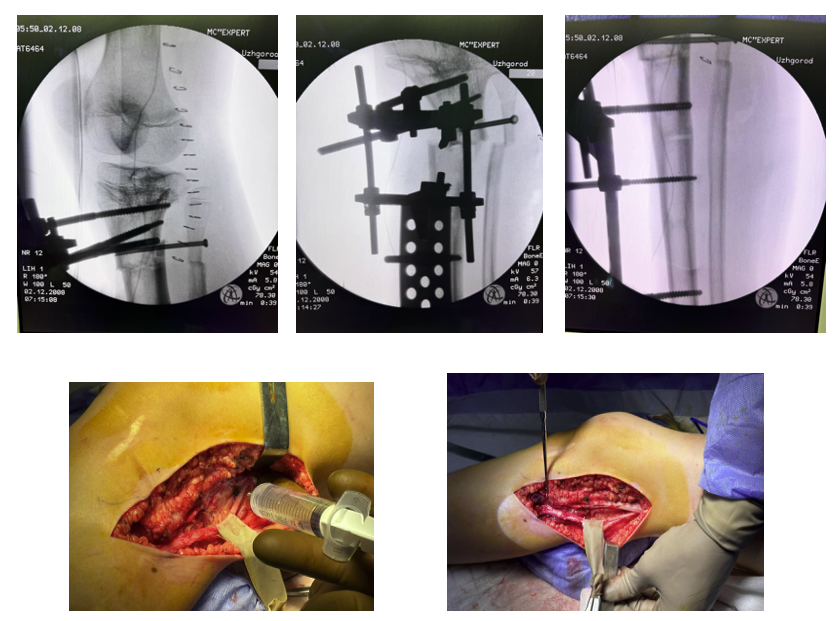

Хірургічне лікування: реконструкція гомілки з використанням сучасних технологій

У лікарні «Експерт» було виконано комплексне реконструктивне втручання. Спочатку проведено розширений реліз м’яких тканин та усунення компартменту малогомілкового нерва лівої гомілки, що важливо для профілактики неврологічних ускладнень. Далі виконана напівзакрита остеотомія малогомілкової кістки та фіксація проксимального міжгомілкового синдесмозу канюльованим гвинтом для стабілізації сегменту.

Наступним етапом став монтаж апарату зовнішньої фіксації на базі стрижнів, що дозволяє точно контролювати положення фрагментів кістки та при потребі здійснювати їх дозоване переміщення. Завершальним етапом була закрита остеоклазія великогомілкової кістки з формуванням умов для подальшої корекції деформації та подовження.